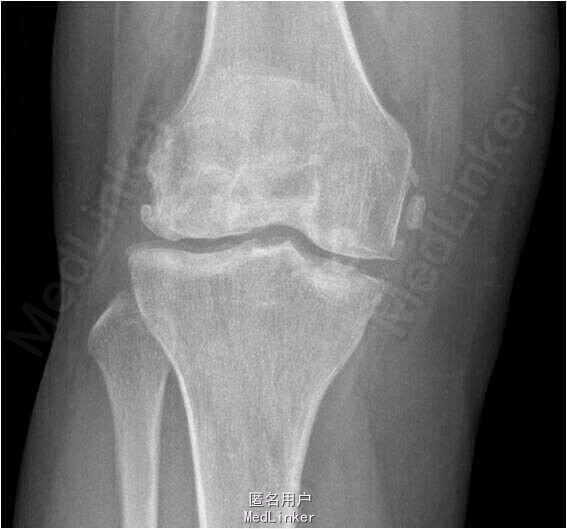

患者男,71岁,因”右膝关节反复疼痛5年余“入院。患者5年前右膝关节无明显诱因出现反复疼痛,偶伴关节绞索,上下楼梯后疼痛加重,休息后稍有缓解,余未见明显异常。

查体:右膝关节活动度20-110°,髌骨加压研磨试验(+)。 X线检查可见右膝关节多发游离体形成。

诊断:右膝关节游离体形成。行关节镜下关节腔清理术及游离体取出术。术后予玻璃酸钠关节腔内注射。